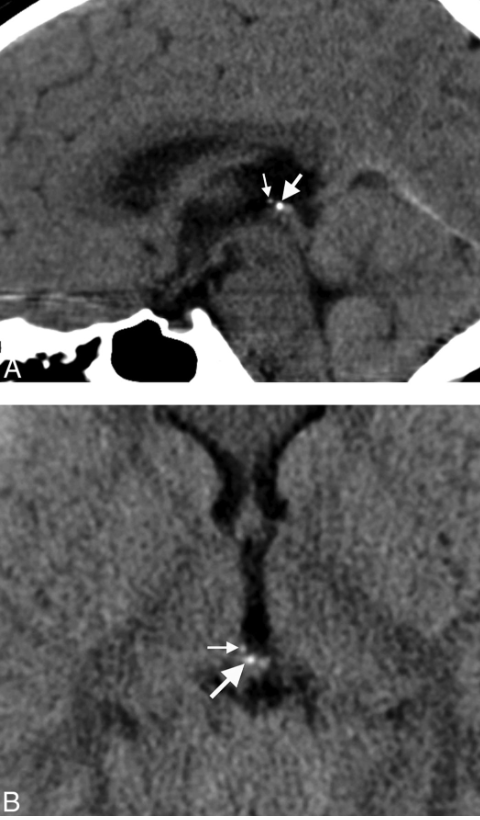

The pineal gland in humans is a small (100-150 mg), highly vascularized, and a secretory neuroendocrine organ (1). It is located in the mid-line of the brain, outside the blood-brain barrier and attached to the roof of the third ventricle by a short stalk. In humans, the pineal gland usually shows a degree of calcification with age providing a good imaging marker (for a speculative discussion of pineal calcification see reference(2)). The principal innervation is sympathetic, arising from the superior cervical ganglia (3). Arterial vascularization of the pineal gland is supplied by both the anterior and posterior circulation, being the main artery supplying the lateral pineal artery, which originates from the posterior circulation (4). In mammals, the main cell types are pinealocytes (95%) followed by scattered glial cells (astrocytic and phagocytic subtypes) (5). Pinealocytes are responsible for the synthesis and secretion of melatonin.

인간에서 송과선은

연령에 따라 석회화 정도를 보이며,

이는 좋은 영상 마커로 사용됩니다(송과선 석회화에 대한 추측적 논의는 참고문헌(2)을 참조하세요).